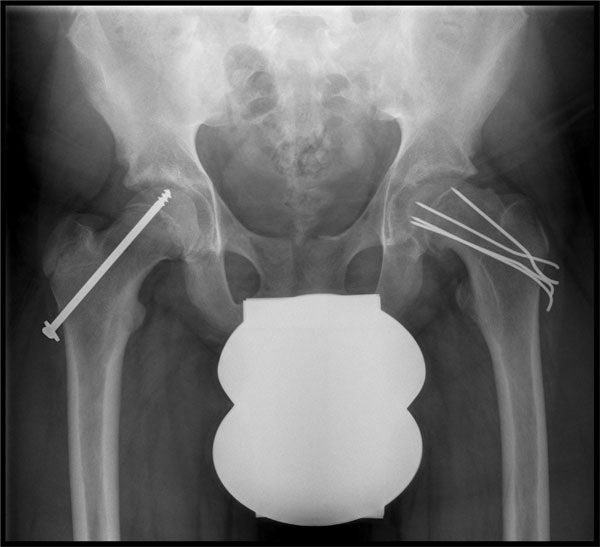

Umstellungsoperation links zur

Verbesserung der Gelenkbeweglichkeit

Ziel ist es, ein weiteres Abrutschen des Hüftkopfes zu verhindern. Der abgerutschte Hüftkopf wird bei der Operation fixiert, z.B. durch Spickung mit Drähten. Da die Erkrankung in vielen Fällen beidseitig auftritt, werden beide Hüftgelenke operativ versorgt. Bei einem schweren Abrutsch ist es häufig notwendig, weitere operative Maßnahmen am Hüftgelenk durchzuführen.